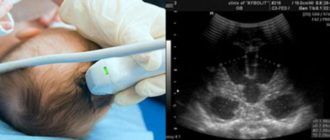

Узи головного мозга у грудничка

Подробно об НСГ головного мозга у детей Неонатальную нейросонографию головного мозга применяют для диагностики

Узи головного мозга у новорожденных и грудничков УЗИ головного мозга у грудничка является самым

Узи головного мозга у грудничка, ребенка до года: узи головы у новорожденных Современные родители,